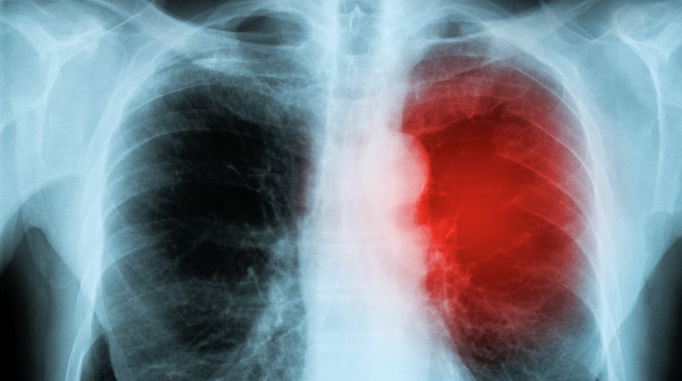

隐球菌肺炎是一种由新型隐球菌感染引起的亚急性或慢性内脏真菌病。该疾病主要侵犯肺部和中枢神经系统,同时也可能波及骨骼、皮肤、粘膜以及其他脏器。本病在青壮年群体中较为常见,而男性患病率明显高于女性。然而,值得警惕的是,隐球菌肺炎的预后十分严重,其病死亡率也居高不下。

隐球菌病是由隐球菌属中的新生隐球菌所引起的一种亚急性或慢性深部真菌病,其特点在于病程相对较长,病情发展较为隐匿。近年来,随着艾滋病的出现和扩散,隐球菌感染的发生呈现出显著的上升趋势,这更为我们敲响了警钟。